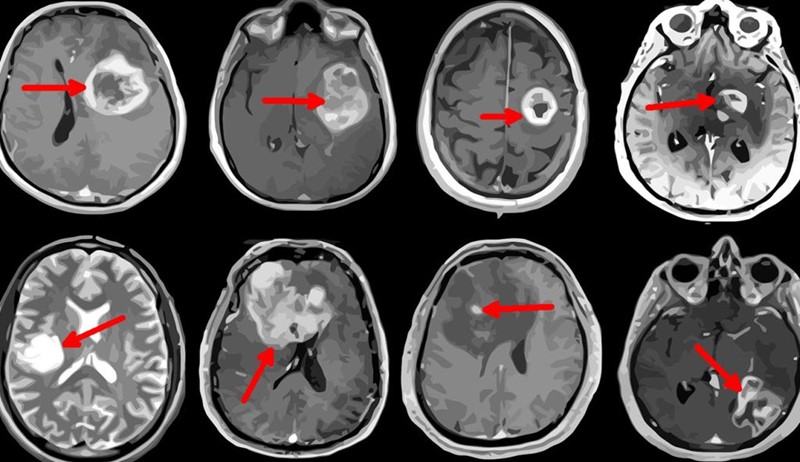

Na Sveučilištu u Pretoriji nalazi se prvi afrički Centar za tumore mozga i translacijsku neuroznanost (BTC@UP), u kojem timovi znanstvenika i neurokirurga testiraju metode kojima bi se preko oka mogli dijagnosticirati ozbiljni poremećaji u mozgu, uključujući i krvarenja i moždane tumore. S druge pak strane Indijskog oceana, u Australiji, istraživači iz Centra za istraživanje oka razvijaju sustave temeljene na umjetnoj inteligenciji koji bi mogli procjenom stanja krvnih žila mrežnice na očnoj pozadini procijeniti u kojoj mjeri imate ili nemate povišeni rizik za srčani ili moždani udar.

A ako mislite da u Africi nedostaje liječnika, pričekajte dok ne čujete statistiku o afričkim neurokirurzima: prosjek je jedan na četiri milijuna stanovnika (u Hrvatskoj je oko 1,5 na 100.000 stanovnika), dok Svjetska zdravstvena organizacija preporučuje omjer 1 na 200.000. Kada se zna da tumori mozga – i benigni i maligni – pogađaju na stotine ljudi (u Hrvatskoj se godišnje dijagnosticira oko 500 novih slučajeva tumora mozga), jasno je da većina oboljelih u zaostalim krajevima i regijama nikada ne dođe do dijagnoze, a kamoli operacije.

Znanstvenici u Pretoriji fokusirani su na moždane tumore i neurološke poremećaje. Triptih dijagnostičkih tehnika koje preporučuju su OUS + IRP + OCT, odnosno: